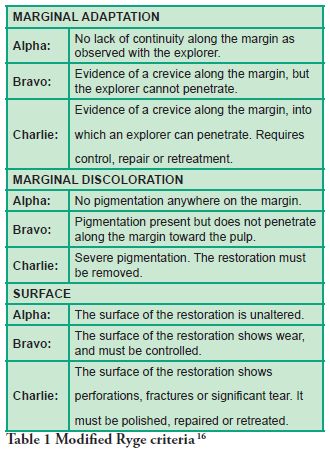

Marginal Adaptation, Marginal Discoloration and Surface were the variables studied to establish the quality of the restorations, following Ryge criteria (16) as modified by the authors (Table 1).

The Success Criteria were defined by the authors according modified Ryge criteria and the statements of Anusavice (17) and grouped as follow: